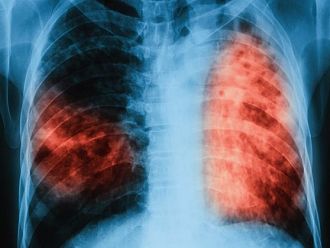

От 18 до 22 март 2019 г. ще се проведат безплатни прегледи за туберкулозa в лечебни заведения за диагностика и лечение на туберкулозата в областните градове на страната, съобщиха от Министерството на здравеопазването.

По време на „Седмицата на отворените врати“ на всеки желаещ се предлага скрининг за риска от туберкулоза чрез анкета и консултации. На лицата, които са в риск, се извършват допълнителни прегледи и изследвания. При откриването на случаи на туберкулоза своевременно се предприемат мерки за хоспитализация и лечение, в резултат на което се прекъсва веригата за предаване на инфекцията.

По време на проведени кампании през месеците март, юни, септември и декември 2018 г. общо анкетирани за туберкулоза са 11 751 лица, като на 6 935 в риск от туберкулоза са извършени медицински прегледи и допълнителни изследвания. Открити са 120 лица с туберкулоза и 359 лица с латентна туберкулозна инфекция, на които е започнато лечение.